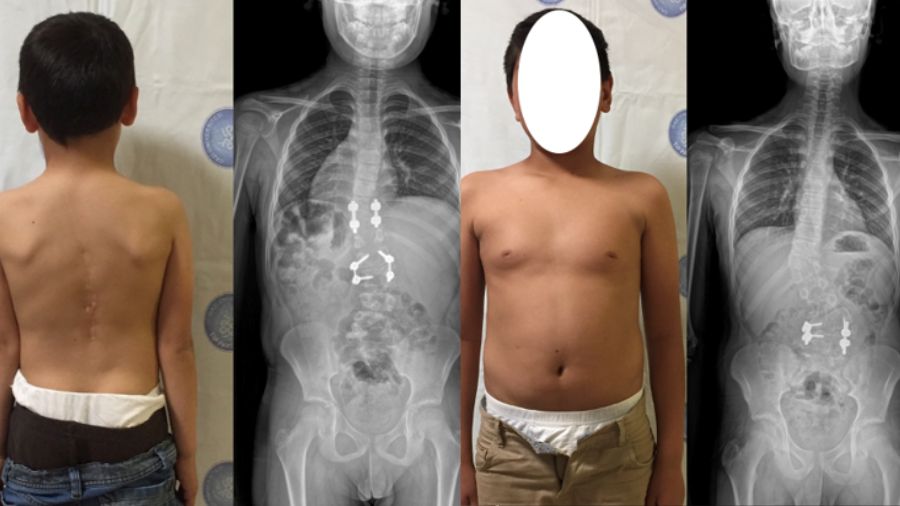

The boys both had contralateral hemivertebra, but with differing degrees of severity, and I followed different treatment strategies for the two patients. The younger boy had a hemivertebra in the middle of the lumbar spine, at L-2, and another in the lower thoracic spine around T-10. The older patient had similar deformity pattern with contralateral lumbar and thoracic hemivertebrae. These patients live in a rural area, otherwise it is likely that the spinal deformity would have been picked up at an earlier stage. Congenital scoliosis can cause a severe deformity of the spine, leading to problems such as respiratory insufficiency and neural impairment.

In the case of these brothers, the older brother’s deformity was relatively well controlled, and upper curvature was quite mild, whereas both curves of younger boy were high magnitude. For the younger sibling I was able to excise both hemivertebrae. With localized problems like this, say two or maximum three segments, we are often able to perform a short segment fusion and excision. If we were to wait for excision of the hemivertebra for a long time, we may end up with a reciprocal change in spinal column and necessity of long fusion construct. By taking action earlier we can arrive at a solution with very limited surgeries and without jeopardizing their maturation and growth.

At the follow-up scans, we found that the younger sibling had recovered very well, and his spine was well aligned. For the older brother, I only removed one hemivertebra, and decided to follow the progress of the other. At the follow-up scans he is not so well aligned - in fact the upper thoracic vertebra is totally unbalanced, creating a deterioration of the curvature in the thoracic part. This is clearly evident in the radiographs but in terms of clinical appearance, he looks fine as you can see in the picture.